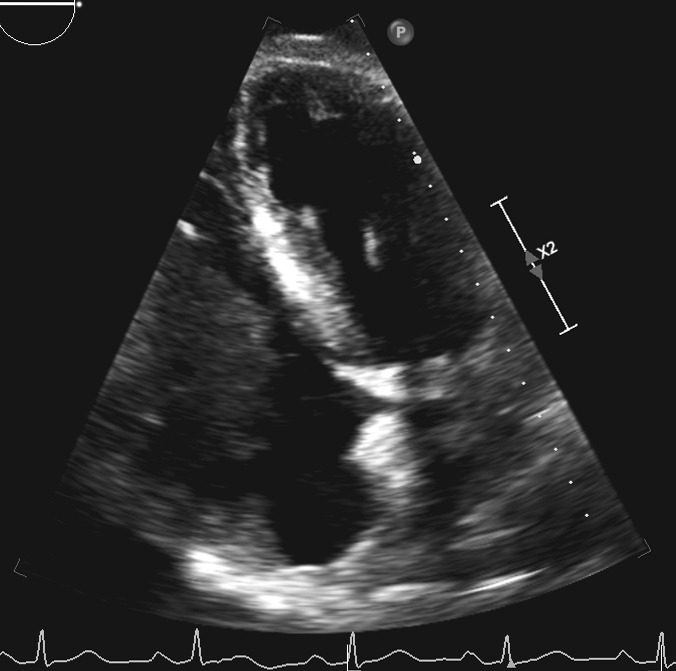

An 81-year-old man with a history significant for hypertension began to experience worsening shortness of breath, fatigue, and lower extremity edema. He was found to have a left upper lobe mass, but a biopsy was non-diagnostic. On further workup, a transthoracic echocardiogram (TTE) showed a large mass within the right atrium, which extended into the right ventricle (Figure 1). The patient had undergone a PET (positron emission tomography) scan, which showed +FDG (fludeoxyglucose) activity within the left upper lobe and mediastinum lymph nodes. The patient underwent a mediastinoscopy and bronchoscopy for tissue but both samples were non-diagnostic. The patient began to show signs of worsening right heart function with increased bilateral edema, elevated jugular venous distention, and complaints of worsening shortness of breath. Cardiac surgery was then consulted for tissue diagnosis and excision of the right atrial mass.

In the operating room, the patient underwent general endotracheal anesthesia. After his sternum had been divided, his right atrium and ventricle appeared distended, and there was evidence of moderate right ventricle dysfunction. On palpation of the right atrium and ventricle, the mass could be easily felt. After Heparin administration, the aorta was cannulated and there was bicaval venous cannulation. The heart was arrested and a right atriotomy was performed. The mass was stuck to the right atrium (Figure 2A and Figure 2B), tricuspid valve, and right ventricle. There was also invasion into the myocardium of the right ventricle. There was no possibility of excision of the mass in its entirety, but multiple biopsies were sent for evaluation (Figure 3). The frozen section returned as lymphoma.